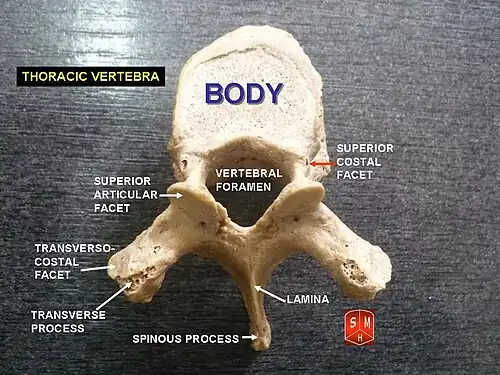

A typical thoracic vertebra, viewed from above.

A typical thoracic vertebra, viewed from above. -

The vertebral bodies in the middle of the thoracic region are heart-shaped and as broad in the anteroposterior as in the transverse direction. At the ends of the thoracic region they resemble respectively those of the cervical and lumbar vertebrae. They are slightly thicker behind than in front, flat above and below, convex from side to side in front, deeply concave behind, and slightly constricted laterally and in front. They present, on either side, two costal demi-facets, one above, near the root of the pedicle, the other below, in front of the inferior vertebral notch; these are covered with cartilage in the fresh state, and, when the vertebrae are articulated with one another, form, with the intervening intervertebral fibrocartilages, oval surfaces for the reception of the heads of the ribs.

The pedicles are directed backward and slightly upward, and the inferior vertebral notches are of large size, and deeper than in any other region of the vertebral column.

The laminae are broad, thick, and imbricated – that is to say, they overlap those of subjacent vertebrae like tiles on a roof and connect with the pedicles to surround and protect the spinal cord.

The intervertebral foramen is small, and circular, with two at each intervertebral level, one for the right and one for the left exiting nerve roots.

The vertebral foramen is the large opening posterior to the vertebral body also known as the spinal canal. It contains and protects the spinal cord at the thoracic level.

The spinous process is long, triangular on coronal section, directed obliquely downward, arising from the lamina and ending in a tuberculated extremity. These processes overlap from the fifth to the eighth, but are less oblique in direction above and below.

The superior articular processes are thin plates of bone projecting upward from the junctions of the pedicles and laminae; their articular facets are practically flat, and are directed backward and a little lateralward and upward.

The inferior articular processes are fused to a considerable extent with the laminae, and project slightly beyond their lower borders; their facets are directed proximally, medially, and inferiorly to the lamina.

The transverse processes arise from the arch behind the superior articular processes and pedicles; they are thick, strong, and of considerable length, directed obliquely backward and lateralward, and each ends in a clubbed extremity, on the front of which is a small, concave surface, for articulation with the tubercle of a rib.